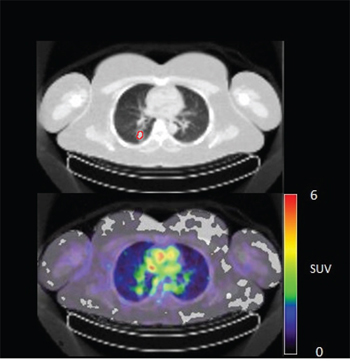

In 6 out of 10 patients, target lesions were visually assessed positive for 89Zr-cetuximab uptake. Figure 4A and 4B shows examples of visible 89Zr uptake in a metastatic lesion of the iliac bone (patient 8) and the lung (patient 10). In Figure 4C, another lung lesion in patient 10 shows no uptake. Most tumor lesions showed increasing uptake in time, indicating accumulation of cetuximab. SUVpeak of these lesions varied between 2.2–7.5 on day 6 p.i.. Figure 4D illustrates the photopenic aspect of liver metastases within normal liver tissue accumulating high amounts of 89Zr-cetuximab. Two of the 3 patients who were scanned at day 10 p.i. had visible 89Zr-cetuximab uptake. SUVpeak at day 10 increased compared to day 6 in patient 8 (from 7.3 to 10.3), but was comparable in patient 6 (3.17 and 3.36, Figure 4E Due to the physical half-life of 89Zr, image quality deteriorated over time, making day 6 p.i. the optimal scanning time point. Visually negative tumor sites had SUVmean of 1.0–1.9 at day 6 p.i. (Figure 5).

Figure 4A: 89Zr-cetuximab PET scan of patient 8 at day 6 p.i. with visible uptake in tumor lesion in the left iliac bone.

Figure 4B: 89Zr-cetuximab PET scan of patient 10 at day 6 p.i. with visible uptake in tumor lesion in the lower lobe of the right lung and low accumulation in surrounding healthy lung tissue.